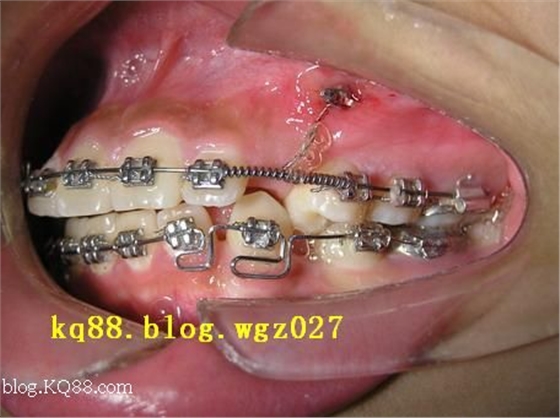

步驟:局麻下在牙冠最易暴露的部位開窗,暴露的牙面應稍大于粘接附件的底板,腎素紗布壓迫止血后,常規(guī)粘結(jié)牽引附件。附件可為托槽、舌側(cè)扣或牽引鉤,待3~5日組織愈合后行牽引導萌。

牽引的力源和方式可為彈力線、橡皮圈、鎳鈦絲輔弓,選擇可根據(jù)病例埋伏牙的情況和醫(yī)生臨床經(jīng)驗而定,牽引力約為30~50g。上尖牙水平阻生的病例可酌情考慮使用人工支點,利用杠桿原理,順阻力最小的地方牽引萌出。

步驟:局麻下去除牙冠的軟硬組織,腎素紗布壓迫止血,用牙內(nèi)科渦輪機倒錐車針制備1.5×1.5mm倒凹洞型,鋼絲小圈與洞形吻合后,清洗、隔濕吹干,玻璃離子充填,鋼絲游離端繞到鎳鈦絲輔弓上。5~7天傷口愈合后加力牽引?;蛑苯訉摻z游離端如螺旋狀繞到鎳鈦絲輔弓上,借助鎳鈦絲的彈性回復力牽引埋伏牙,每次復診纏繞一周,也可將末端做成鉤狀,采用彈力線或橡皮圈牽引。